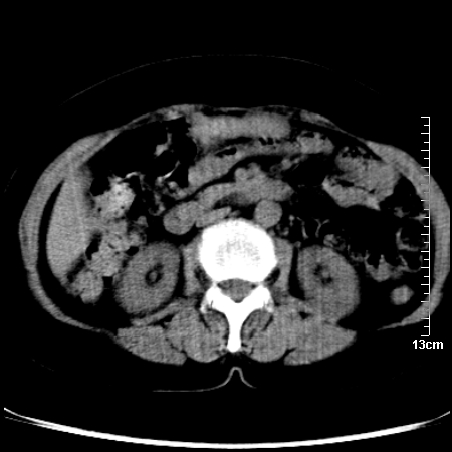

巨大囊实性包块,边界大部尚清楚,不太像脓肿的表现。应该做个增强检查除外盆腔肿瘤。

脓肿可能性大. 因回盲部区域化脓性兰尾切除残端感染改变征像与实性肿块关系密切.肿块上界至右下腹,下界至盆腔膀胱上缘, 如果是实性肿块在兰尾术中可能就会发现. 所以术后一周病人高烧, 白细胞增高,临床表现支持脓肿.

盆腔一边界大部份清晰囊实性肿块,其周腹脂未见确切异常,其一端与右侧附件相连。考虑右侧附件肿瘤。

如果能进行肠道准备就好了!盆腔内巨大囊实性包块,右前缘与周围肠管分界不清,病灶内前部的气体是否为肠管内气体形成的假象不能确定。

这么大一包快手术当中没有发现?值得怀疑!结合化脓性阑尾炎病史,首先考虑脓肿!不排外附件来源的肿瘤,建议增强扫描!!